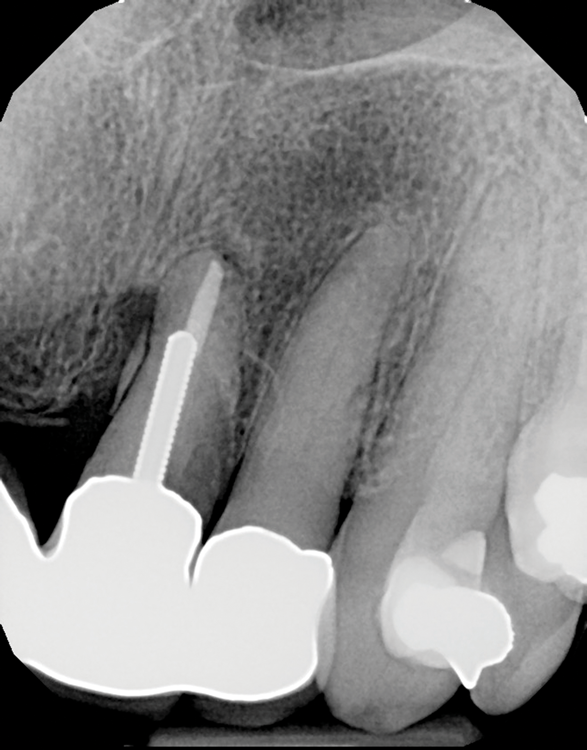

(3.) Radiograph of a loose screw-style metal post.

Figure 3